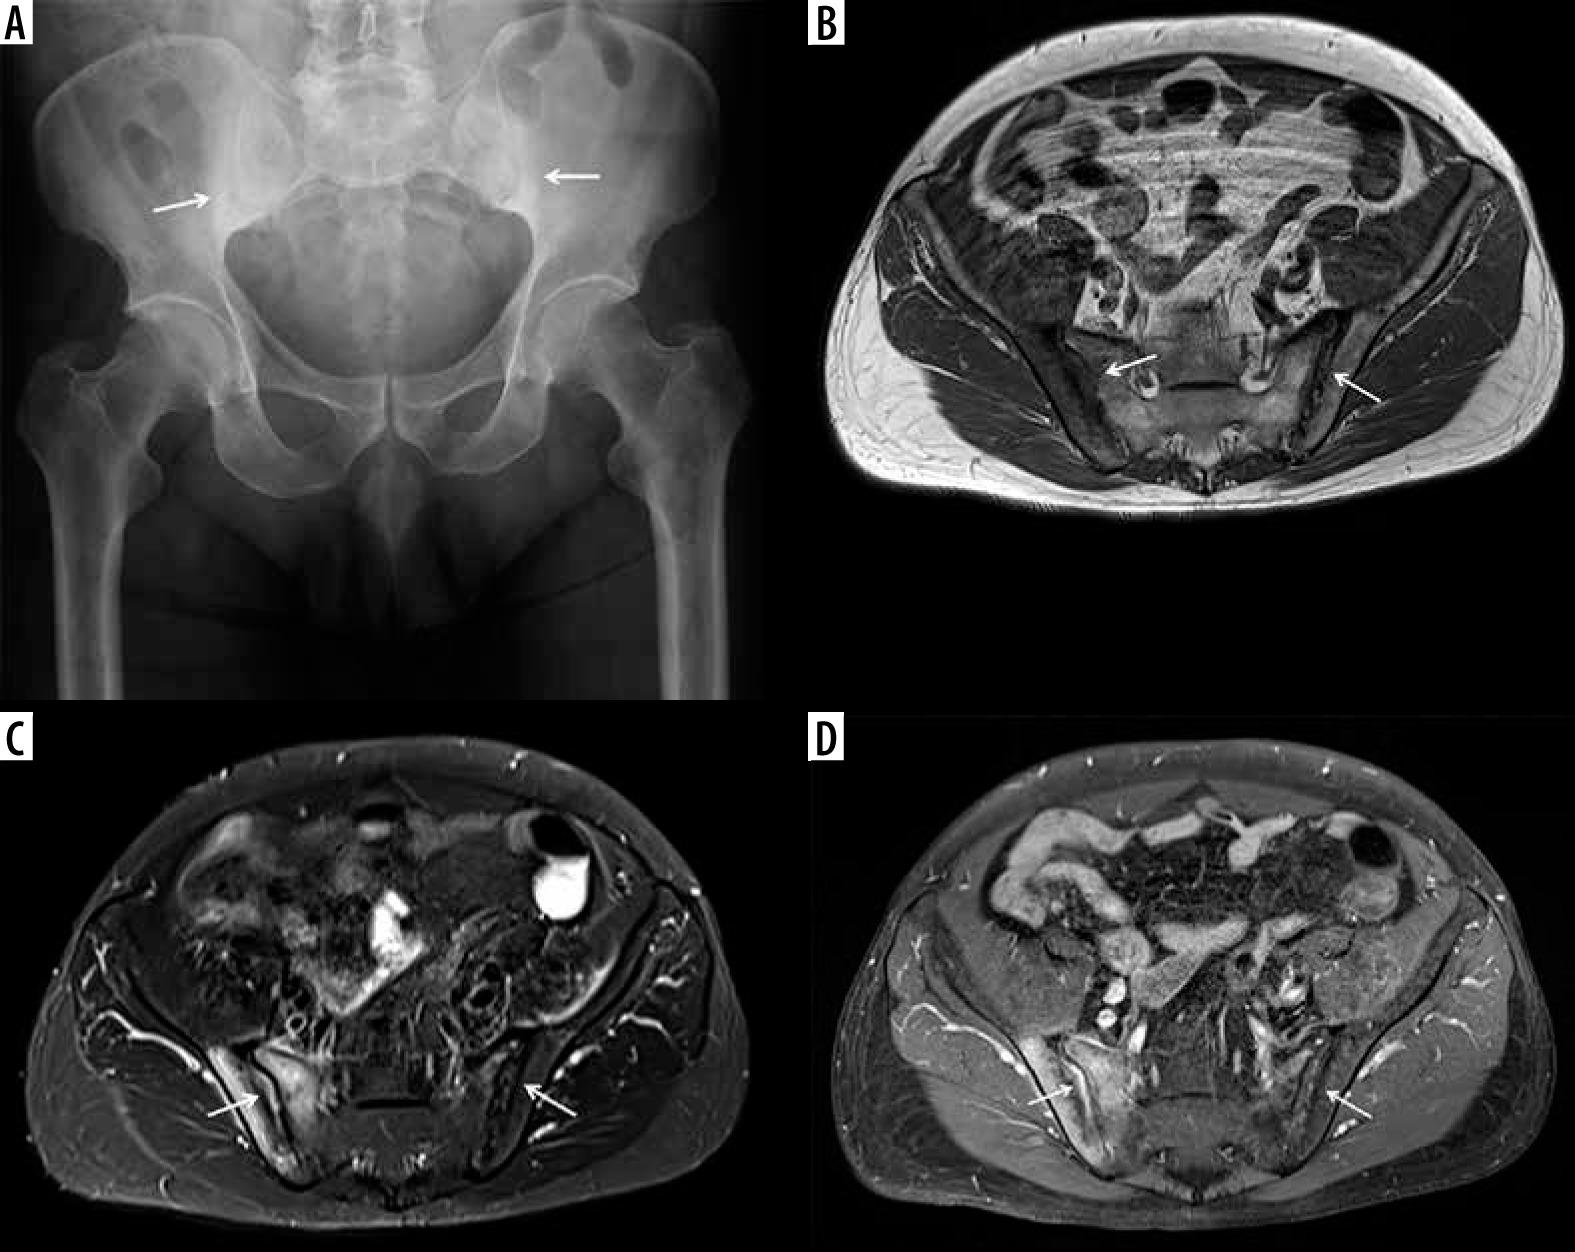

Figure 15

A 61-year-old male with ankylosing spondylitis (AS) and bilateral sacroiliitis. A) Anterior posterior (AP) radiograph of the pelvis shows subchondral sclerosis and cortical irregularities consistent with erosive bone changes about both sacroiliac joints related to sacroiliitis (arrows). B) Axial T1-weighted (T1W), (C) axial short tau inversion recovery (STIR), and (D) axial T1-weighted with fat-saturation (T1W FS) post-contrast magnetic resonance (MR) images of the pelvis redemonstrate erosive bone changes involving both sacroiliac joints with associated bone marrow oedema (BMO), significantly more pronounced about the right sacroiliac joint, showing intermediate signal intensity in B, high signal intensity in C, and enhancement in D consistent with chronic active sacroiliitis. Note enhancing synovial fluid complex in the right sacroiliac joint related to active synovitis